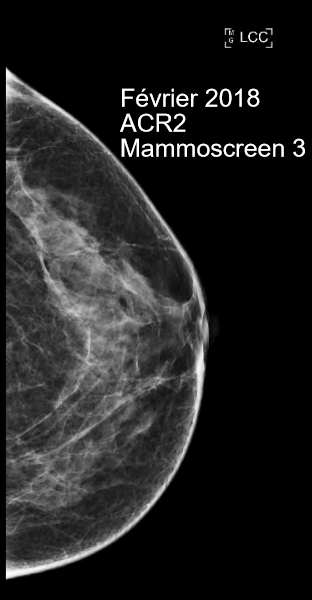

In February 2018, an ACR2-rated screening exam was performed, the MammoScreen Score™ was of 3, with no specific suspicions on the left.